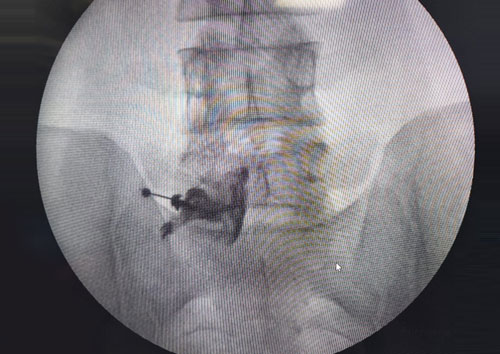

Advanced Pain Management Techniques

1. Selective Nerve Root Block for Lumbar Disc Prolapse

Selective nerve root blocks are a vital tool for diagnosing and treating lumbar disc prolapse. This procedure involves injecting anesthetic and, when appropriate, corticosteroids near the affected nerve root. By targeting specific areas, we can alleviate pain caused by nerve compression and reduce inflammation, providing both immediate relief and valuable diagnostic information.